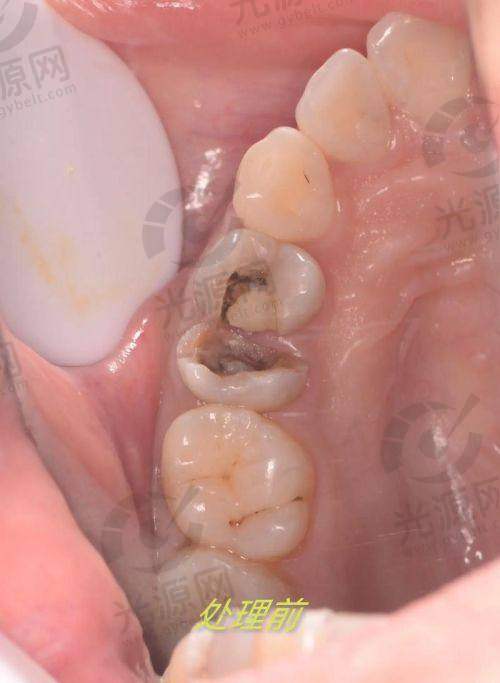

武汉固康口腔注重基础口腔医疗服务,医院拥有名列前茅的诊疗环境和专精的医生团队,特别擅长根管治疗、补牙等基础项目。固康口腔以合理的价格和贴心的服务,赢得了患者的认可,并在各类口腔疾病的防治上有独到的见解和治疗方案。